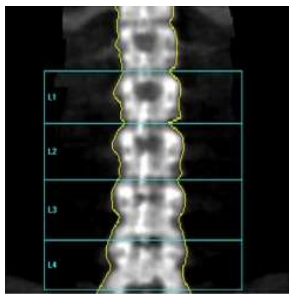

Assinale a alternativa que apresenta qual o erro na aquisição da imagem abaixo.

Rotação da coluna

Aquisição insuficiente, não pegou a crista ilíaca

Artefato de movimentação

Presença de vértebra de transição

Contagem errada das vértebras